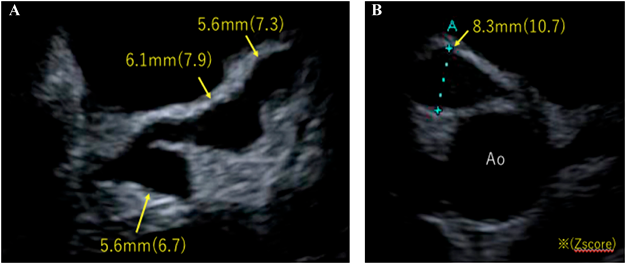

Angiography 1 month later revealed four medium-sized aneurysms on the left coronary artery (6 mm on LMT, 6.9 mm and 6.8 mm on LAD, 4.4 mm on the left circumflex coronary artery) and one giant aneurysm (15 mm) on RCA (Fig. 2).

Fig. 2 Angiography one month after the onset of KD showing four medium-sized aneurysms on the left coronary artery (A) and one giant aneurysm on the right coronary artery (B)

LAO, left anterior oblique; RAO, right anterior oblique.